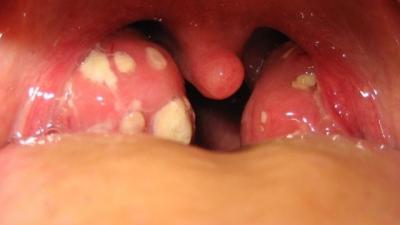

На Луганщине зафиксирован и лабораторно подтвержден первый случай заболевания дифтерией.